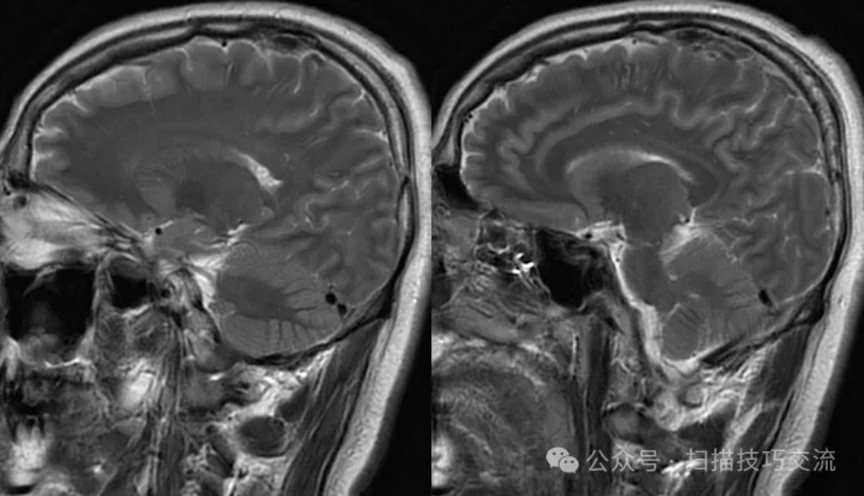

临床申请:颅脑平扫,静脉成像,磁敏感成像,颅内静脉血管黑血成像。

PC-MRV未见异常。